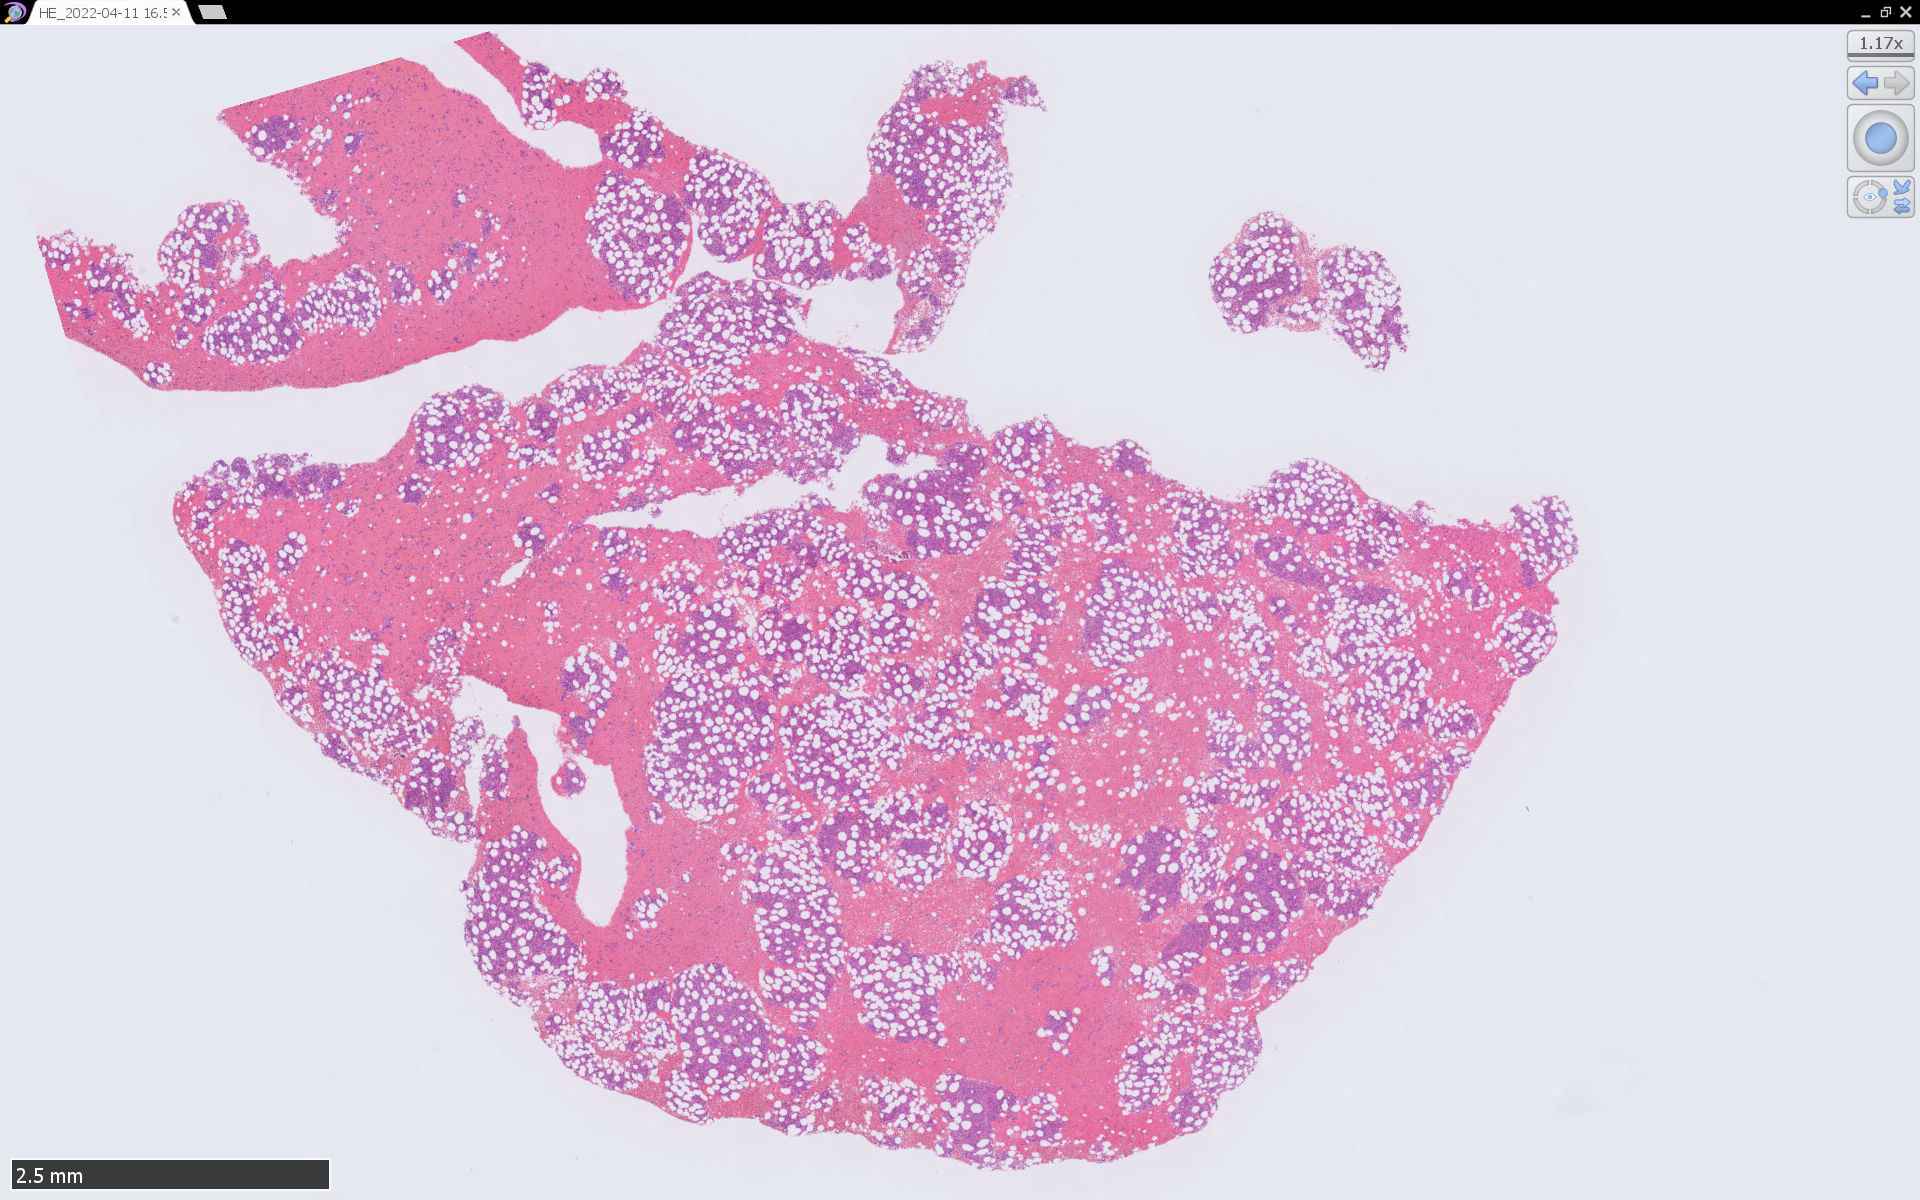

骨髄病理所見

組織, 細胞病理

皮膚病変

IWT-case: 4つの点で囲んだ紅斑から生検.

皮膚病変は64-100%の症例で認められ皮膚病変が契機となり診断されることも多い.

マクロ所見は多彩で, 孤在性から播種性の分布を呈し, 腫瘤, 局面, 紅斑いずれの形態もとりえる.

腫瘍細胞は真皮を主座として, 皮下脂肪織まで, びまん性かつ単調monotonousに増殖することが多く, 表皮向性はみられない.

腫瘍は形態の異なる2種類の細胞の均一単調な増殖からなる.*4

1. classical BPCDN

腫瘍細胞核は中等大, 不整形. クロマチンは繊細で, 核小体は不明瞭か, 1ないし数個. 細胞は狭小から中程度の量の細胞質をもつ.

2. immunoblastic BPCDN*2*3*4

類円形空胞状核, 好塩基性で中等量の細胞質,大きな光輝性の中心性核小体を1個もつ免疫芽球(immunoblast)に似た細胞の増殖が主体.